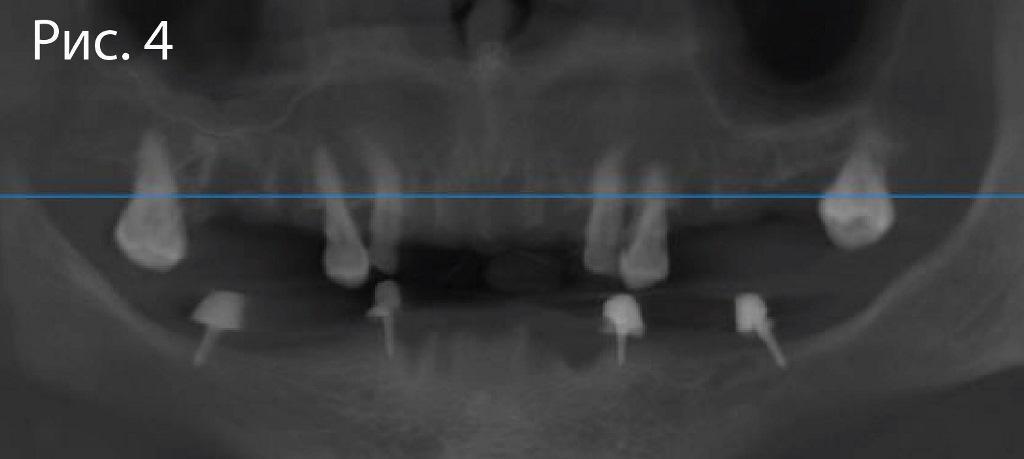

Женщина, 57 лет. Вовлеченные зубы: верхняя и нижняя челюсть. Основные жалобы: боль, отечность мягких тканей на обеих челюстях.

Диагноз: дефицит доступного объема кости для имплантации

До